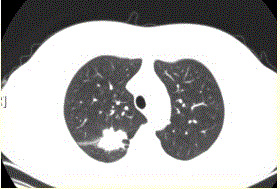

问题 患者女,54岁,无症状,常规体检透视时发现右上肺阴影。既往无结核病史。体格检查阴性。CT结果如下图。 易出现空洞的肺癌类型是

选项 A.鳞癌 B.腺癌 C.未分化癌 D.肺泡癌 E.转移性肿瘤 F.肺类癌

答案 A

解析 A